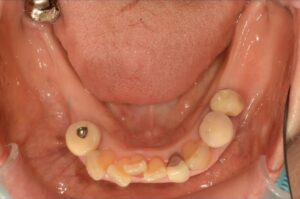

Before

| 年齢・性別 | 82歳、女性 |

| 治療期間・回数 | 4ヶ月間、来院回数4回 |

| 治療方法 | 歯と歯の間に0.5mmのやすりがけをして歯の横幅を修正し、マルチブラケット装置(ワイヤー矯正器具)にて歯を配列 |

| 費用 | 検査料 55,000円 基本矯正料 220,000円 処置料 5,500円 / 月 |

| デメリット・注意点 | 唇に装置が当たって口内炎になる可能性 歯根吸収の可能性 調整のたびに2〜3日程度、上下の歯が接すると痛みが生じる |